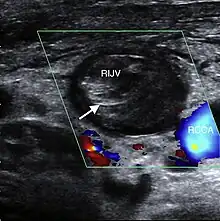

| A post-operative internal jugular vein thrombosis on the person's right | |

| Diagnostic method | Ultrasound, CT scan[1] |

Diagnosis may be suspected based on the D-dimer and confirmed by ultrasound or CT scan.[1]